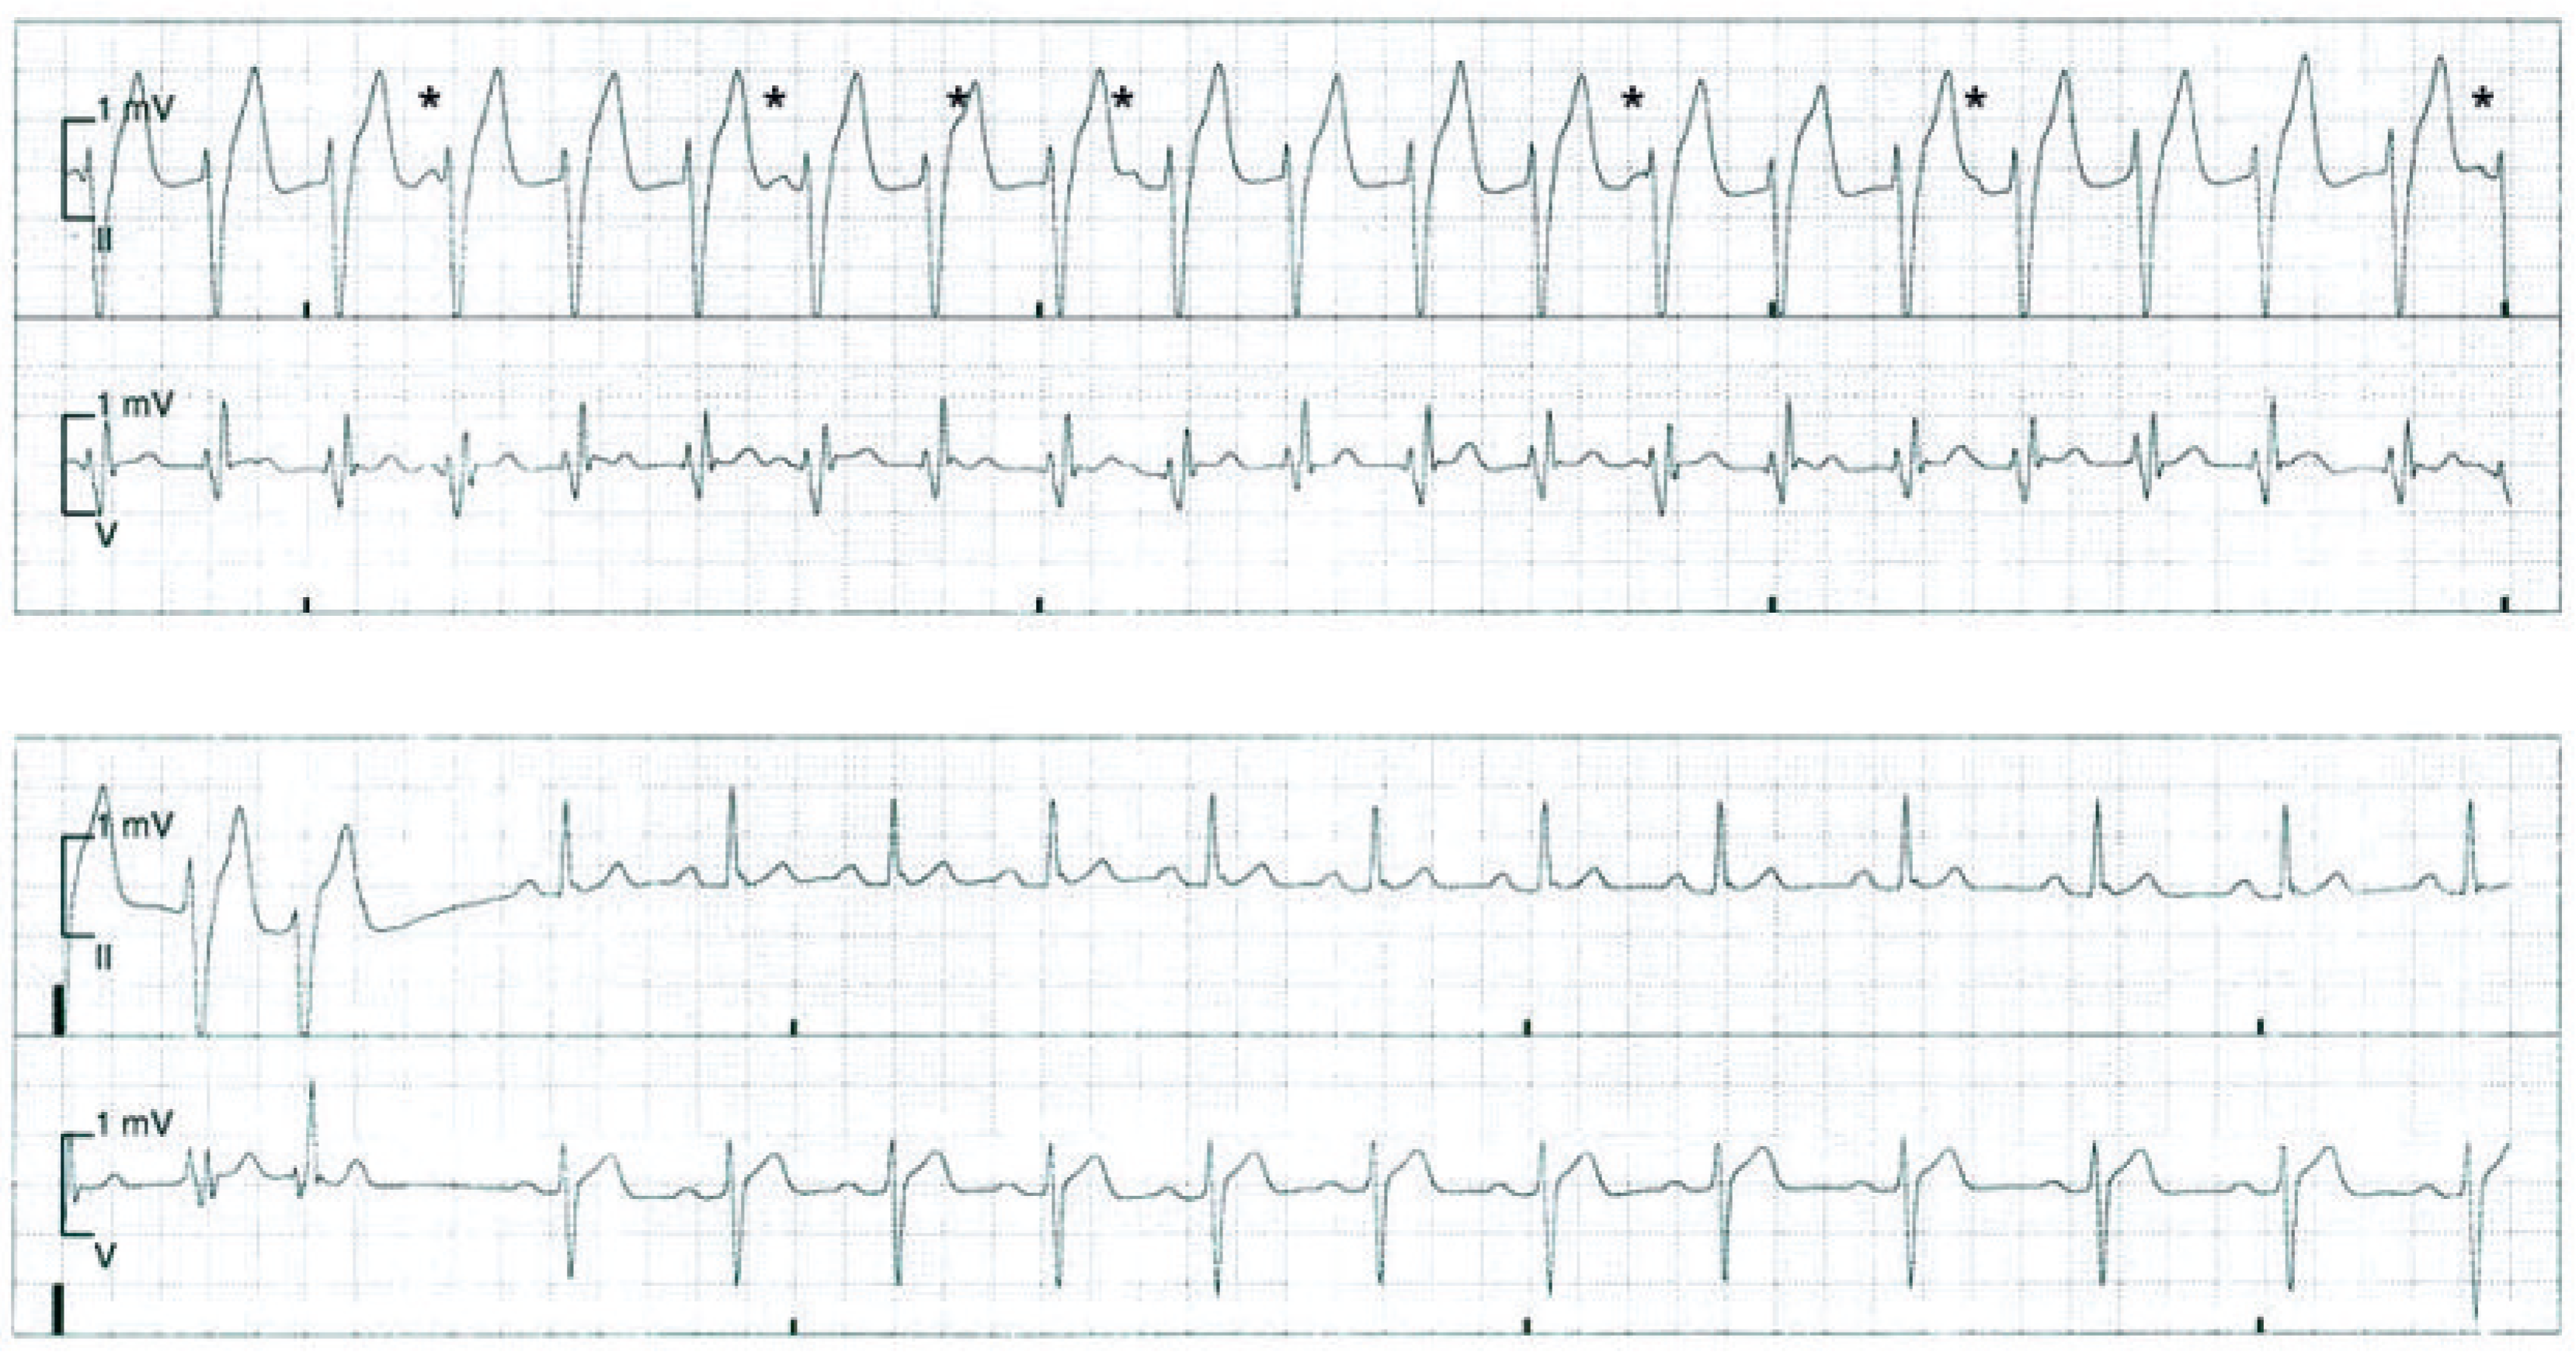

Während eines Spitalaufenthalts wegen der Resektion einer arterio-venösen Malformation am Fussrücken klagte ein 23-jähriger Patient plötzlich über regelmässiges Herzrasen mit einer Frequenz von 140/min (Abb. 1). Der Patient berichtete, seit einigen Jahren rezidivierend einen hohen Puls sowie Palpitationen zu verspüren, vor allem in Stresssituationen. Thoraxschmerzen, Dyspnoe, Schwindel oder Synkopen hingegen wurden negiert. Der kardiopulmonale Status war bland, das EKG in Ruhe unauffällig und die Echokardiographie normal.

Abbildung 1.

12-Kanal-EKG eines 23-jährigen strukturell herzgesunden Patienten mit regelmässiger Tachykardie.